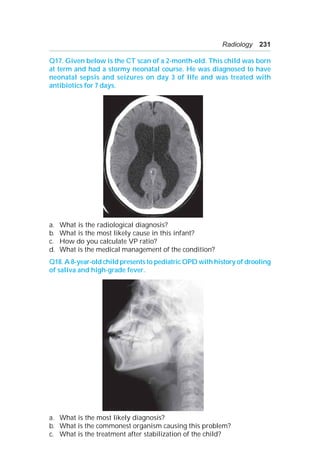

a. List the positive findings on chest X-ray.

b. What is the likely diagnosis?

c. List 3 most important steps in management of this neonate.

Q28. A preterm ventilated baby had a hemodynamic compromise of

sudden onset. The chest X-ray is given below.

a. What is the diagnosis?

b. List two bedside procedures, which could have helped in confirming

the diagnosis before performing the X-ray.

c. What is the definitive treatment in this neonate?

d. What is the treatment option if the infant was asymptomatic?